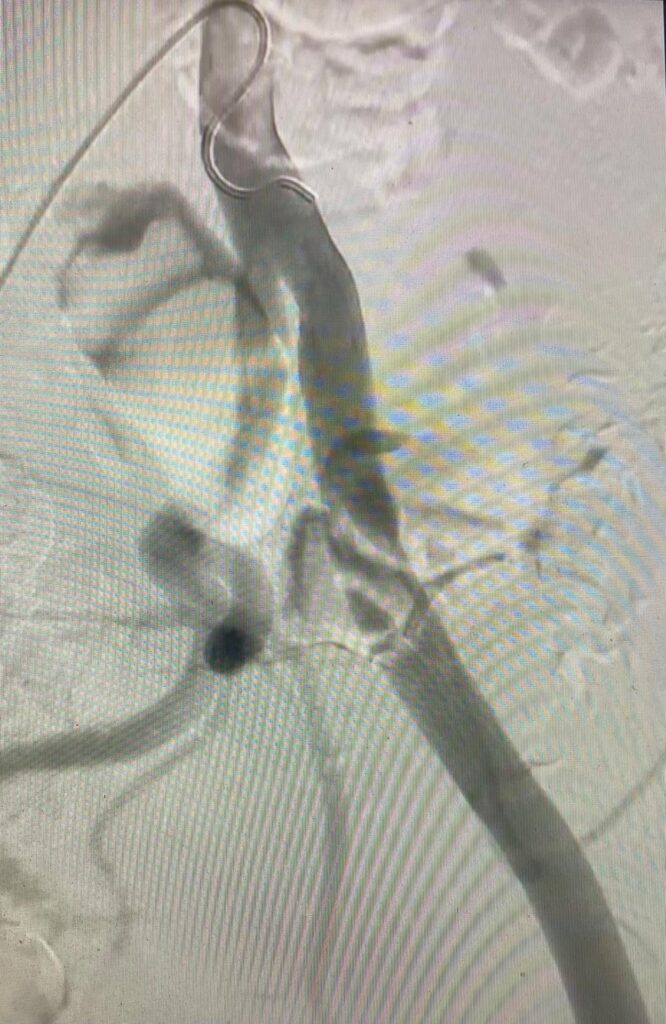

Recientemente he intervenido un nuevo caso de endofibrosis de la arteria ilíaca externa en un ciclista profesional, con afectación del sector ilíaco izquierdo. Se trata de una patología poco frecuente, característica de deportistas de resistencia, que se manifiesta mediante claudicación durante el ejercicio en ausencia de enfermedad aterosclerótica clásica.